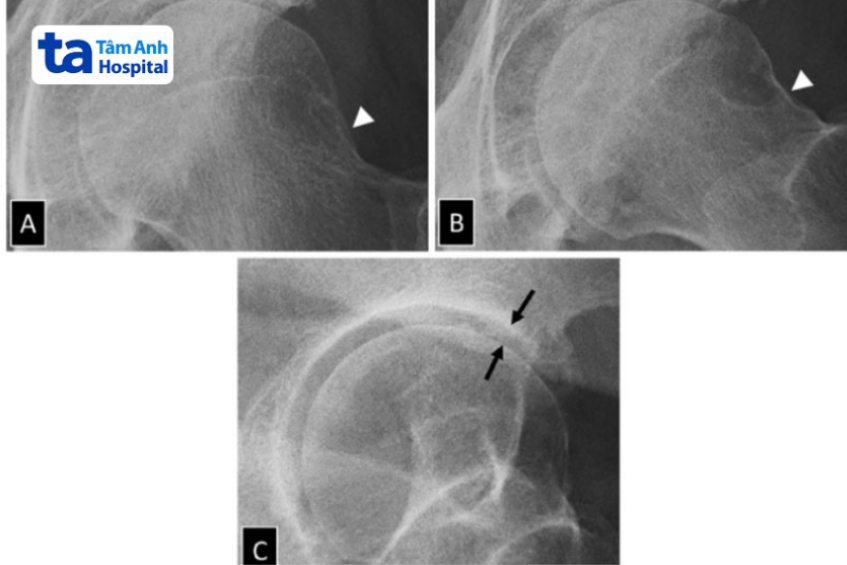

Chụp X-quang có thể được xem là phương pháp chẩn đoán hình ảnh viêm khớp háng đơn giản nhất và có chi phí rẻ nhất. Thông qua kết quả chụp phim X-quang, bác sĩ có thể quan sát được cấu trúc xương và tình trạng chấn thương ở các mô mềm xung quanh (nếu có). Trên phim X-quang không thể thấy được tình trạng sụn khớp, nhưng bác sĩ có thể chẩn đoán viêm khớp háng gián tiếp thông qua khoảng cách giữa xương đùi và ổ cối xương chậu.

Chụp cắt lớp (CT) là phương pháp chẩn đoán hình ảnh viêm khớp háng sử dụng tia X tương tự chụp X-quang nhưng hiện đại hơn. Hình ảnh chụp CT có độ tương phản tốt, có thể dựng hình xương 3D một cách hoàn hảo giúp bác sĩ quan sát và đánh giá tình trạng khớp háng với nhiều góc nhìn khác nhau. (2)